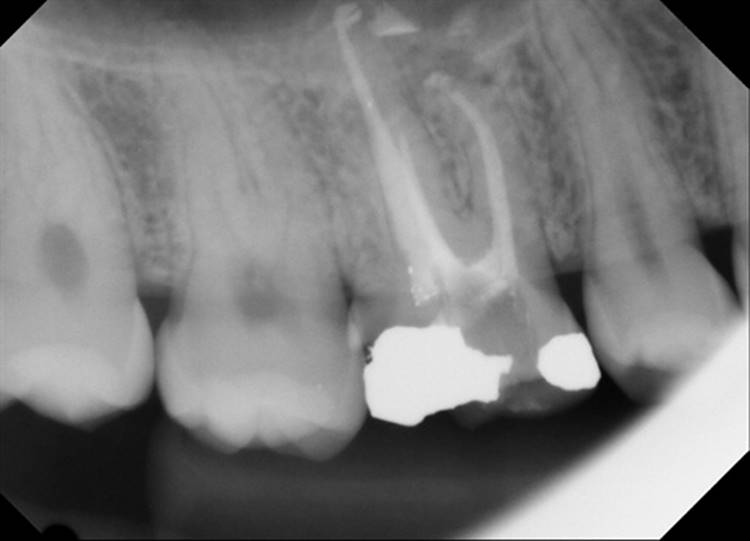

Forgive the sensor change from the first two cases to the last two. The good sensor broke and the back up isn’t as great.

EdgeFile® Cases